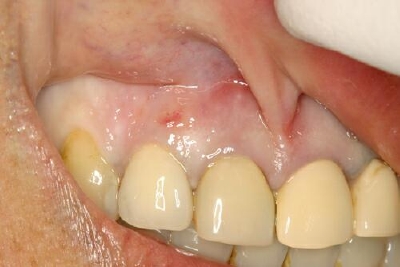

今年最後のインプラント手術は、前歯部の抜歯と同時にインプラントを埋入

仮歯まで切開なしで行った難しい症例でした

抜歯直後 無切開で、周囲骨を壊さないように細心の注意を払って抜歯しました

歯肉縁下6mm 口蓋側よりに埋入

ヒーリングアバット装着

Nobel Active 3.5-11.5mm

理想的なポジションに埋入できました

40Nでたため仮歯まで同時につくります

仮歯装着 この時点では咬ませていないため

やや短いですが、本歯は長さも揃えますよ

ここまでで2時間かかりましたが1日で仮歯まで入るので

歯がない状態で帰る事はありません

傷が治るまでこのまま4〜6ヶ月待って、本歯に仕上げていきます

アクセスホールもなかなかいい位置にきています

手術1週間後 無切開なので大きな腫れや痛みもなく順調です